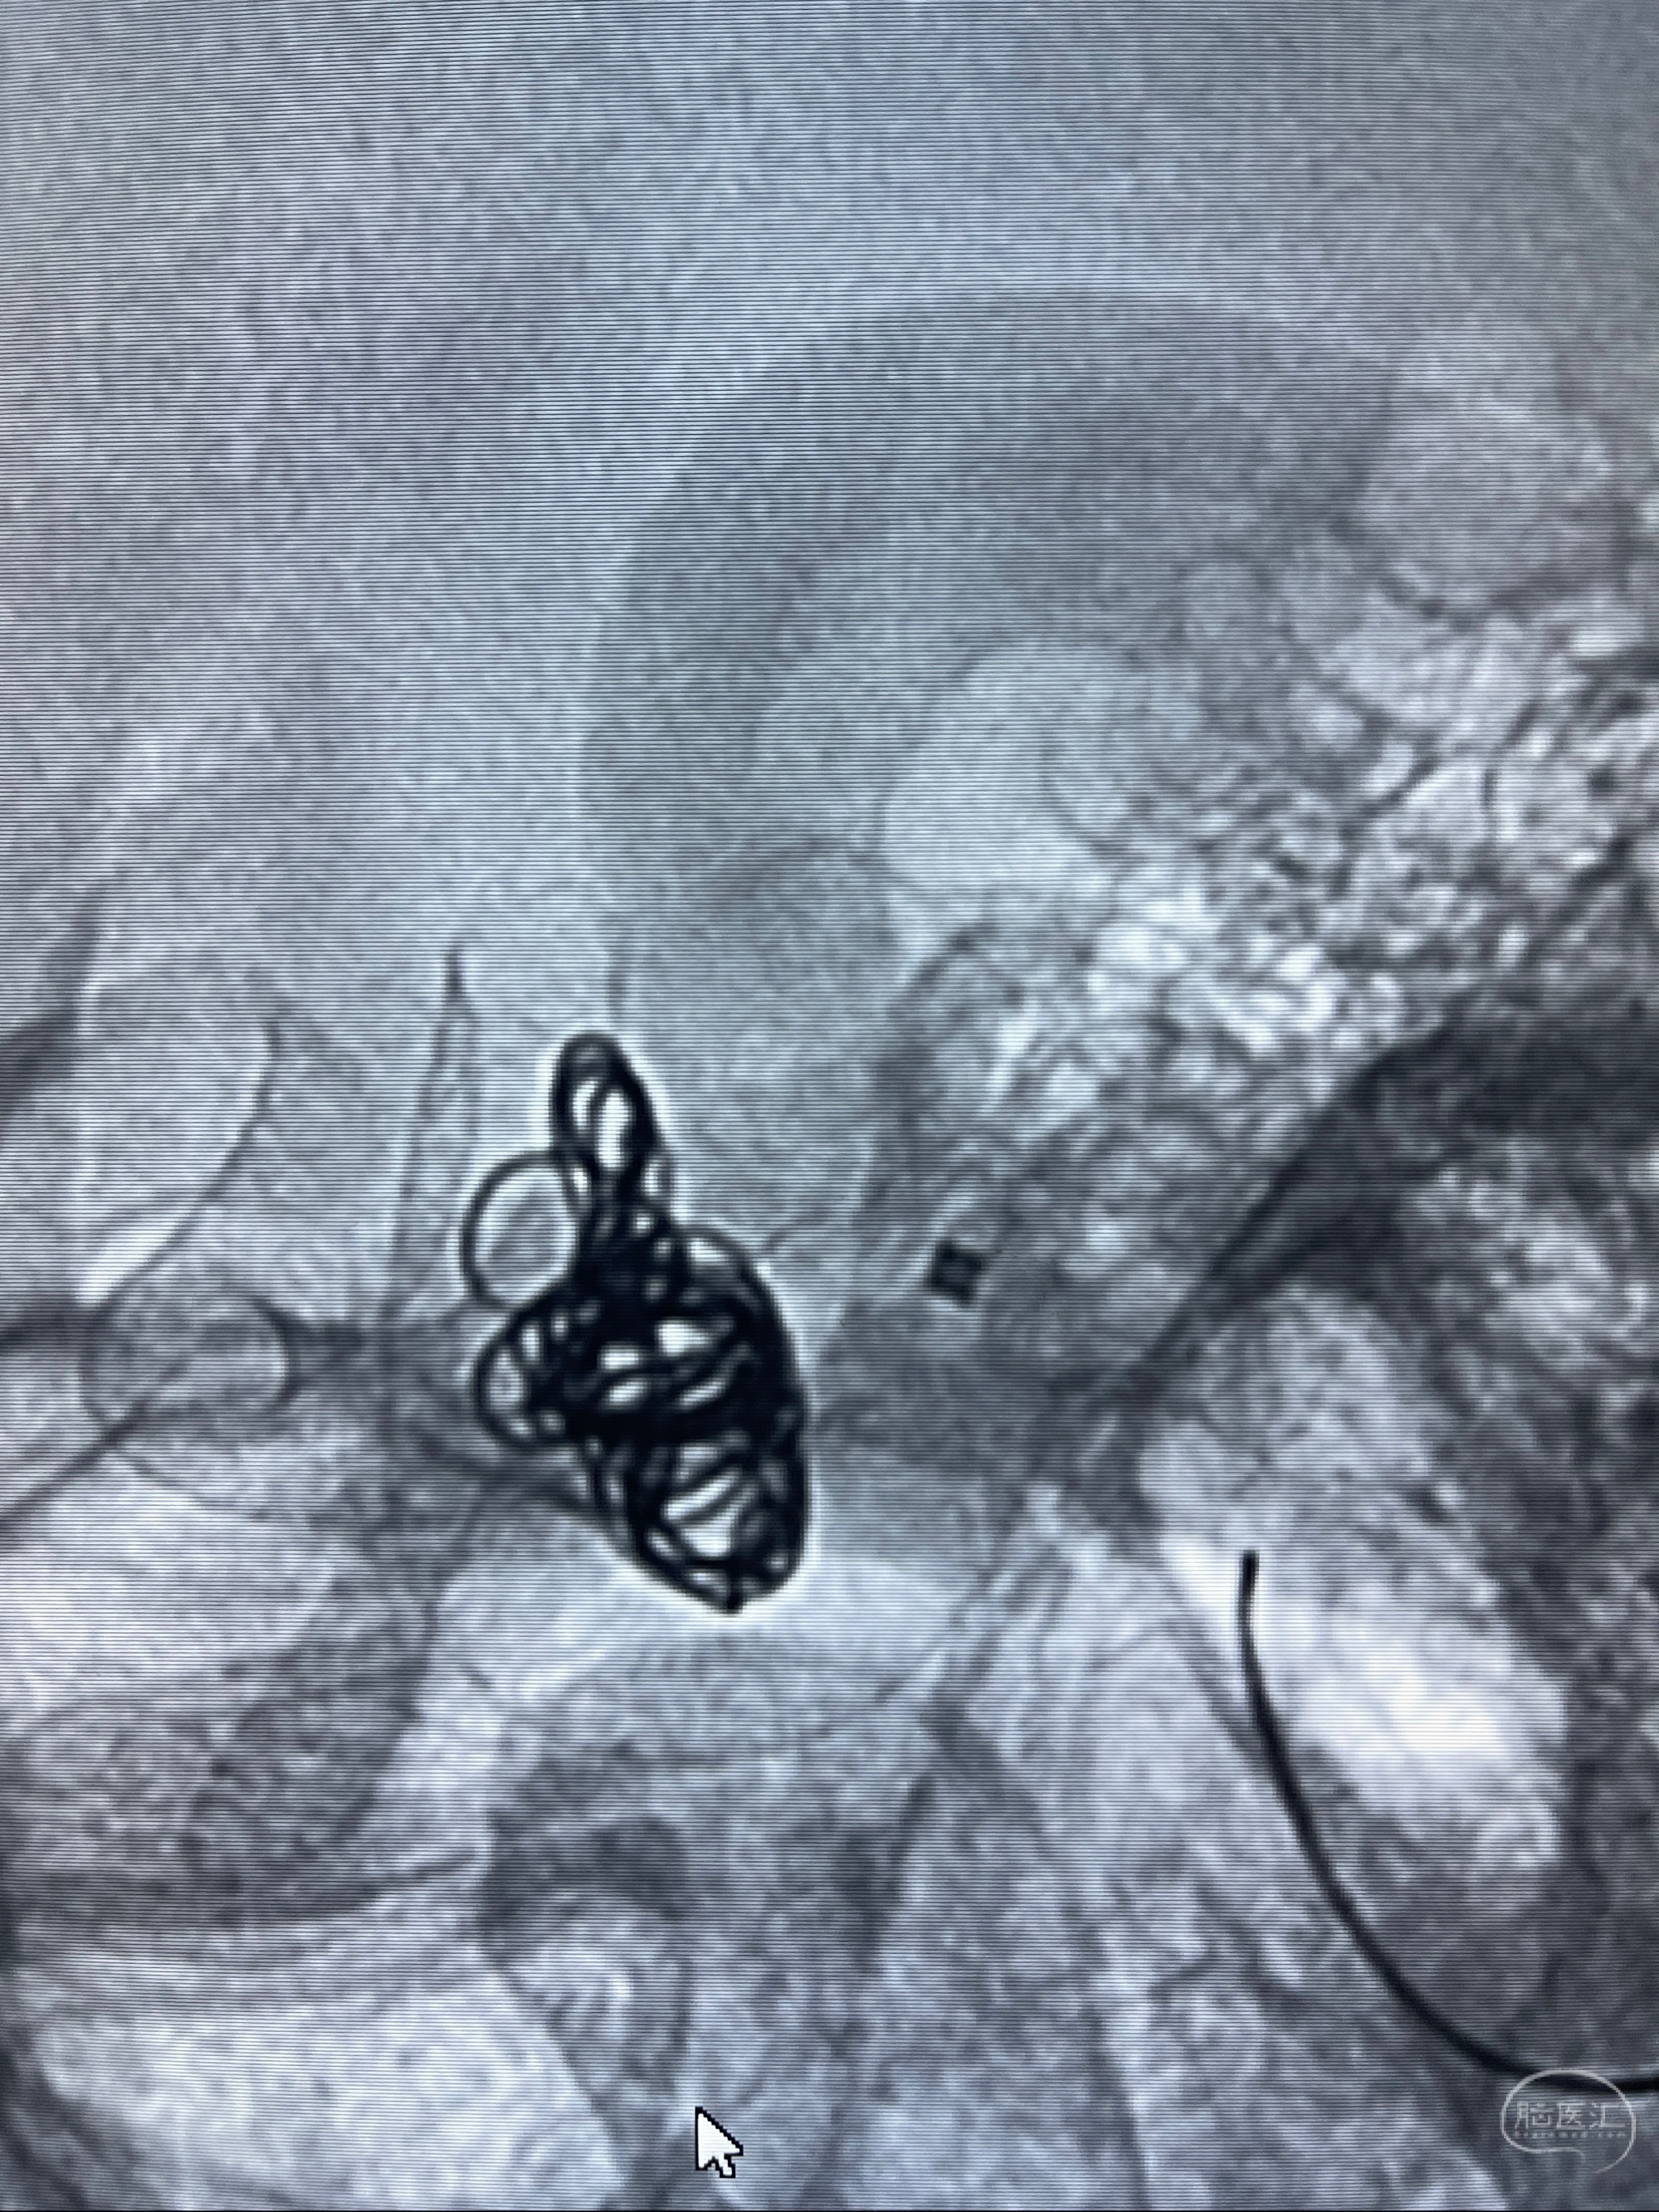

2023-07-27全脑血管造影:双侧颈内动脉眼动脉段动脉瘤,右侧较大

2023-08-01全麻下行双侧颈眼动脉瘤支架辅助栓塞

- pipeling4.5-20mm

- pipeline 4.0-20mm